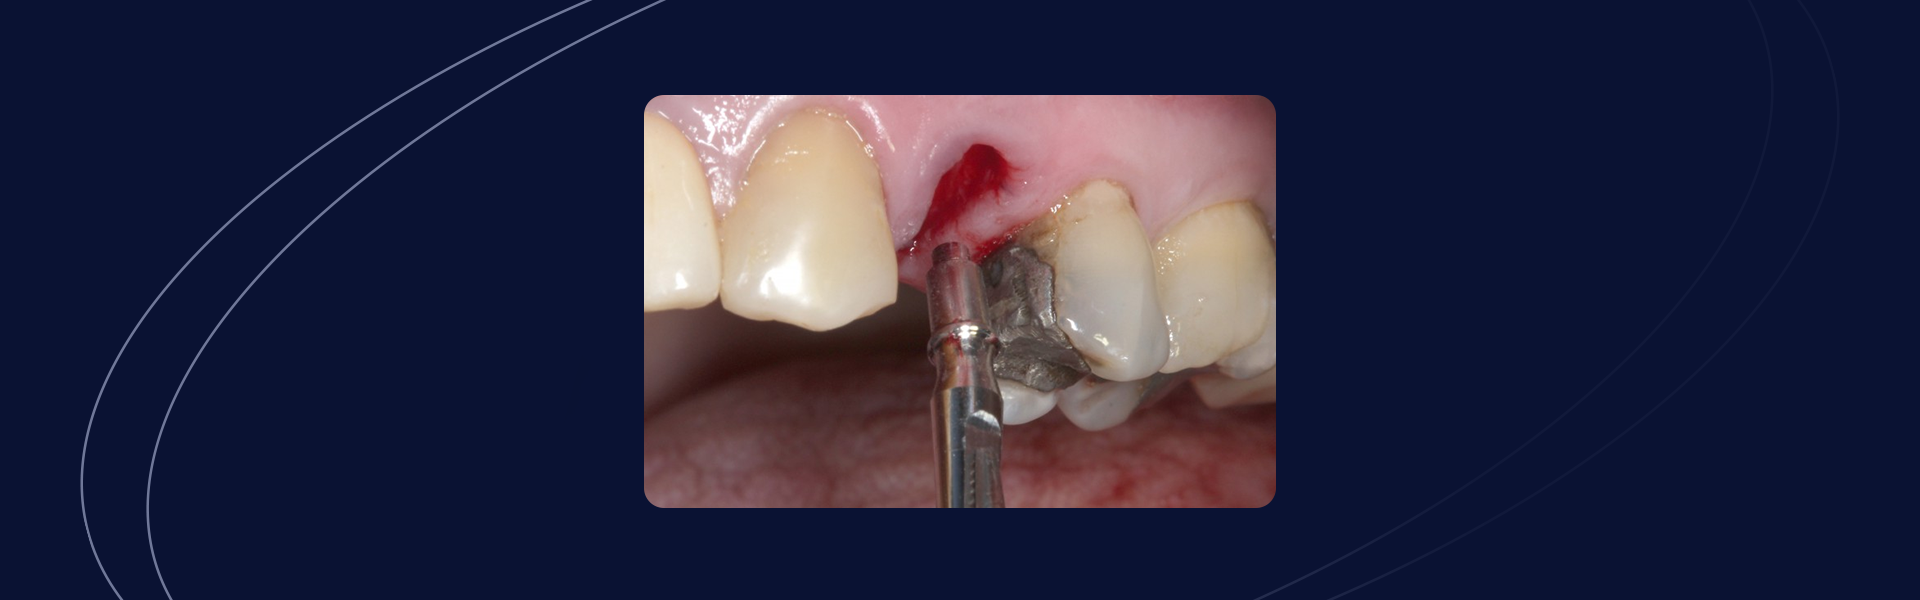

Preenchimento Alveolar de Elemento Posterior com Fratura Associada à Restauração de Amálgama

Autor: Thiago Roberto Gemeli Amplas restaurações de amálgama comumente estão associadas à fraturas dentais, que por vezes, podem comprometer a permanência desses elementos em função. Quando a substituição de um elemento dentário por um implante se faz necessário e possível, uma série de avaliações locais são realizadas para tornar o resultado mais assertivo e previsível. […]